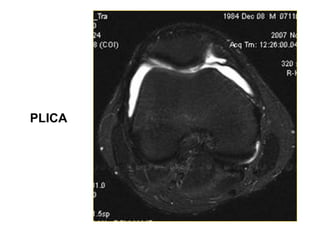

PLICA